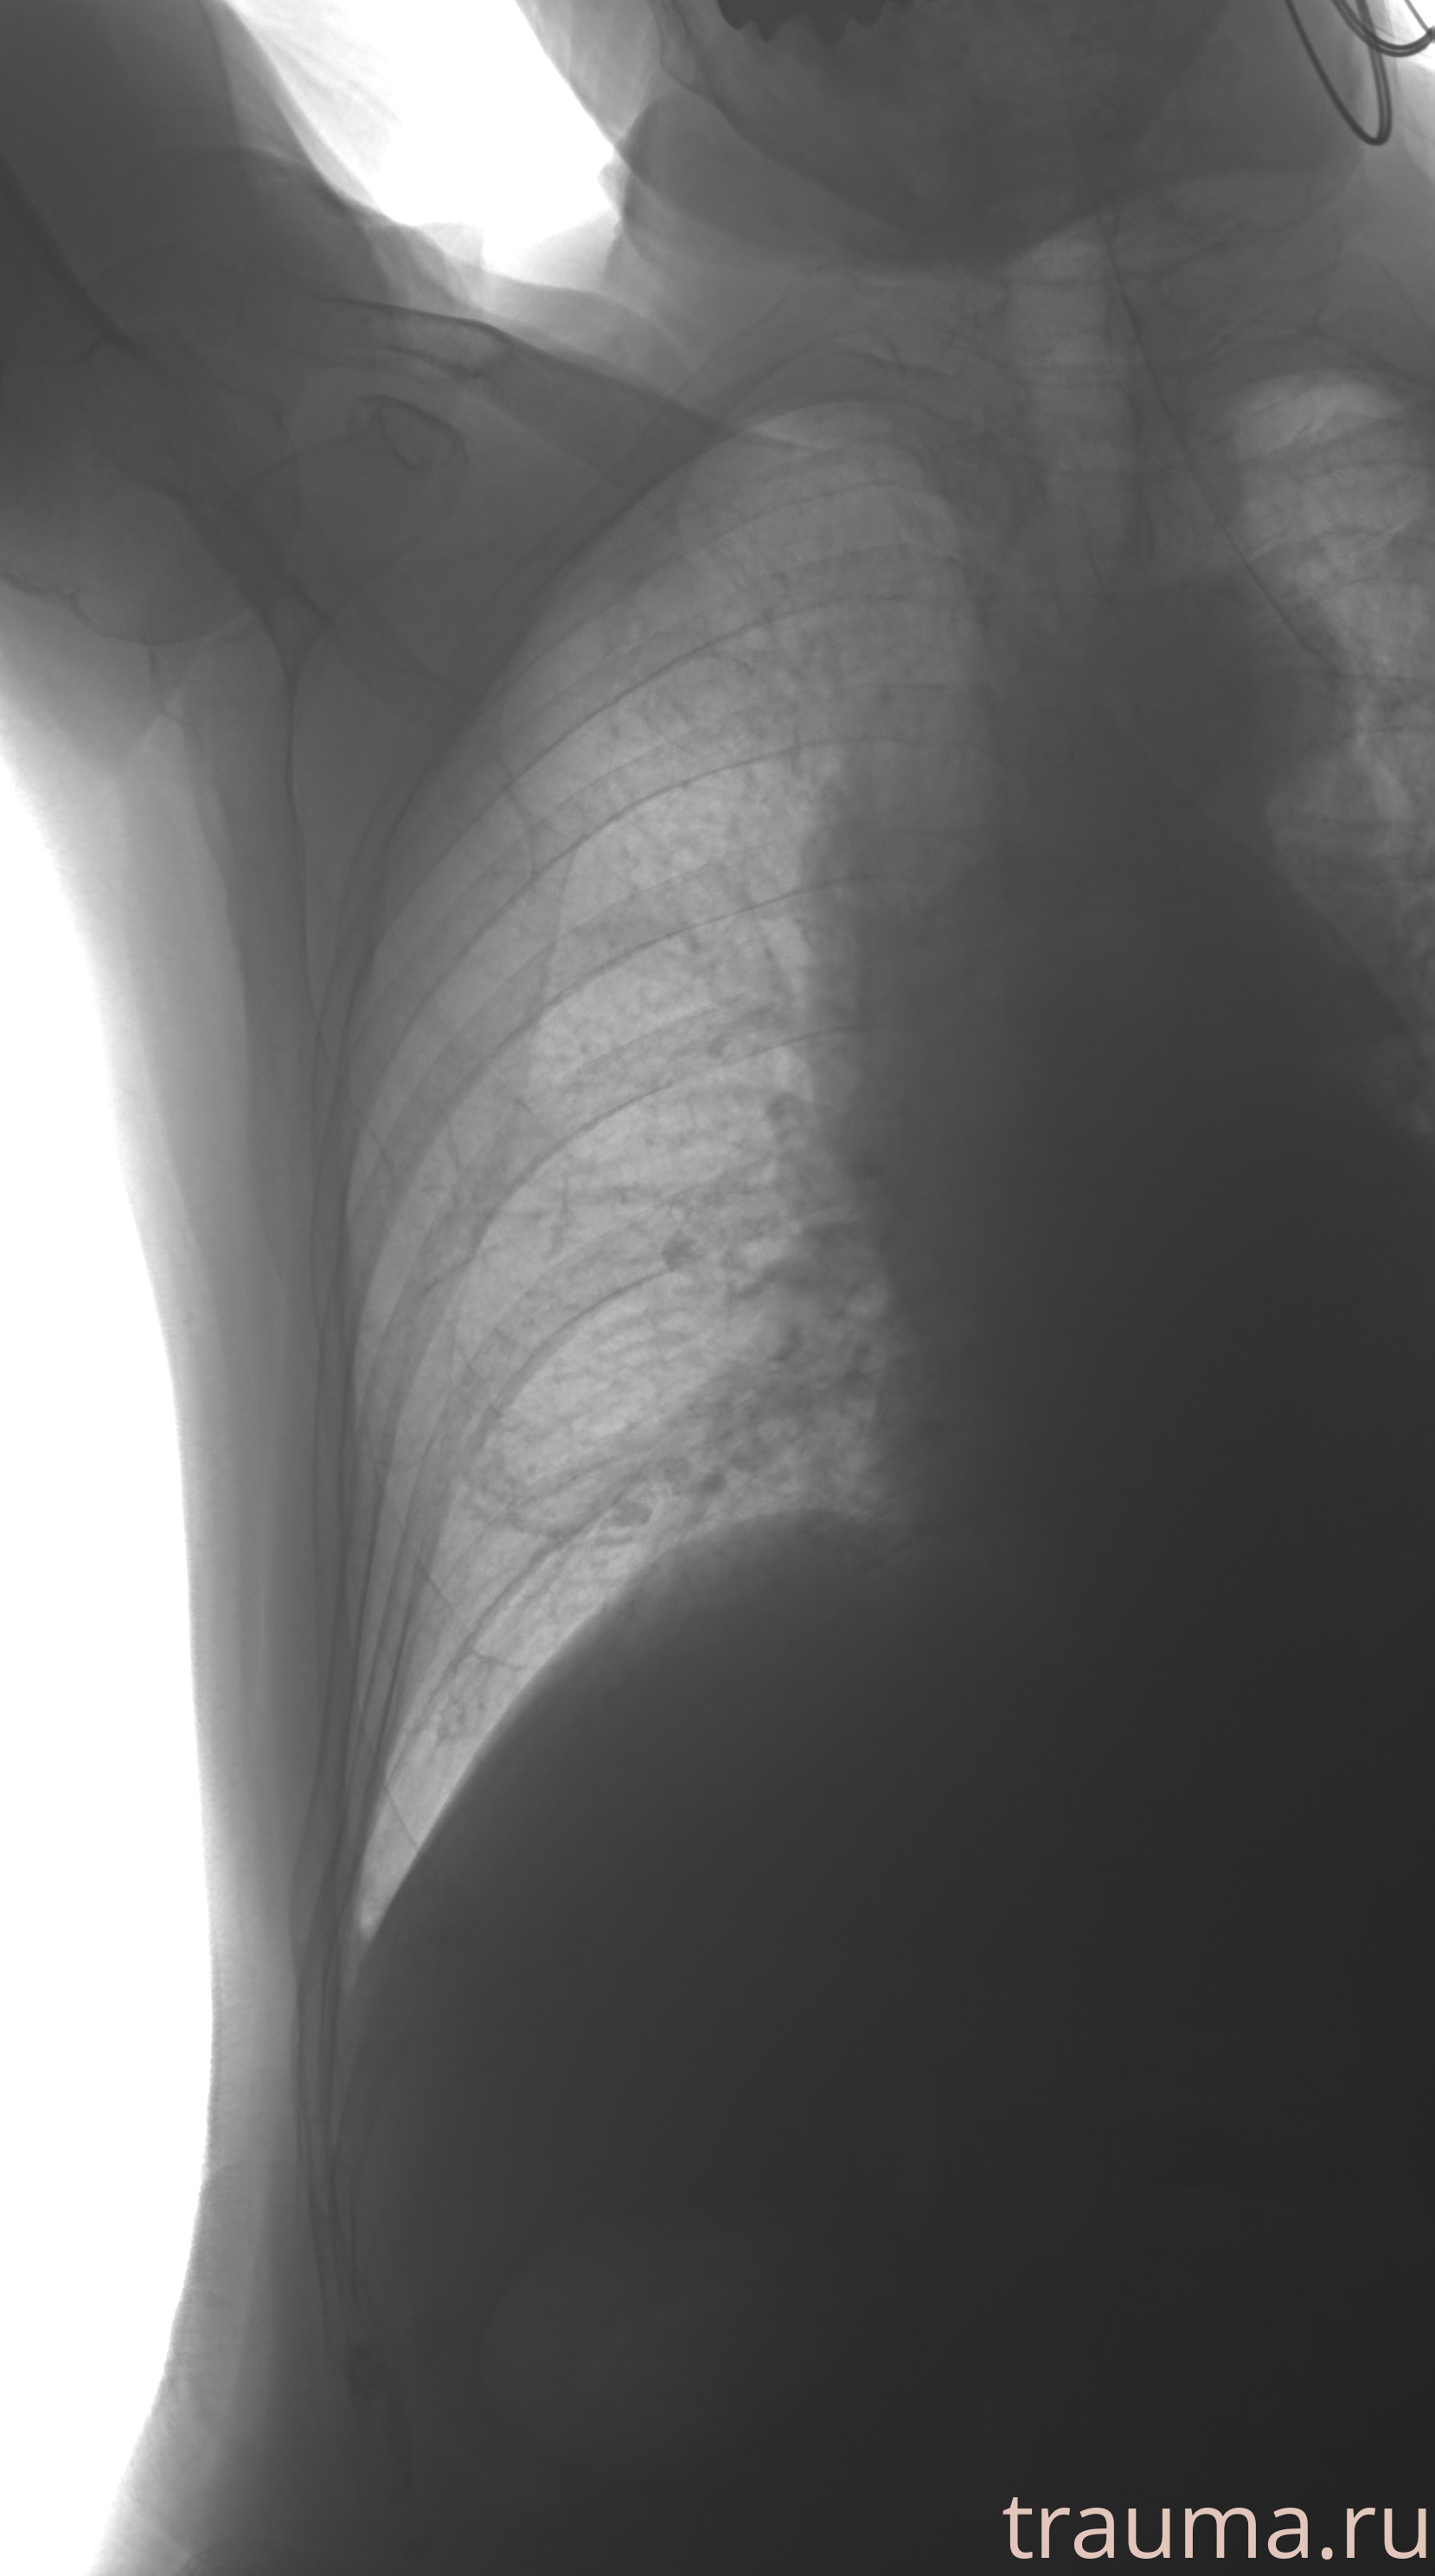

Рентген на дому: по вашему адресу приезжает врач-рентгенолог, травматолог-ортопед с мобильным рентгеновским аппаратом, проводит диагностику травмы или заболевания, делает необходимые рентгенограммы, дает рекомендации по дальнейшему лечению. Получить качественные снимки в домашних условиях возможно благодаря уникальной методике, разработанной МосРентген Центром для института  Склифосовского